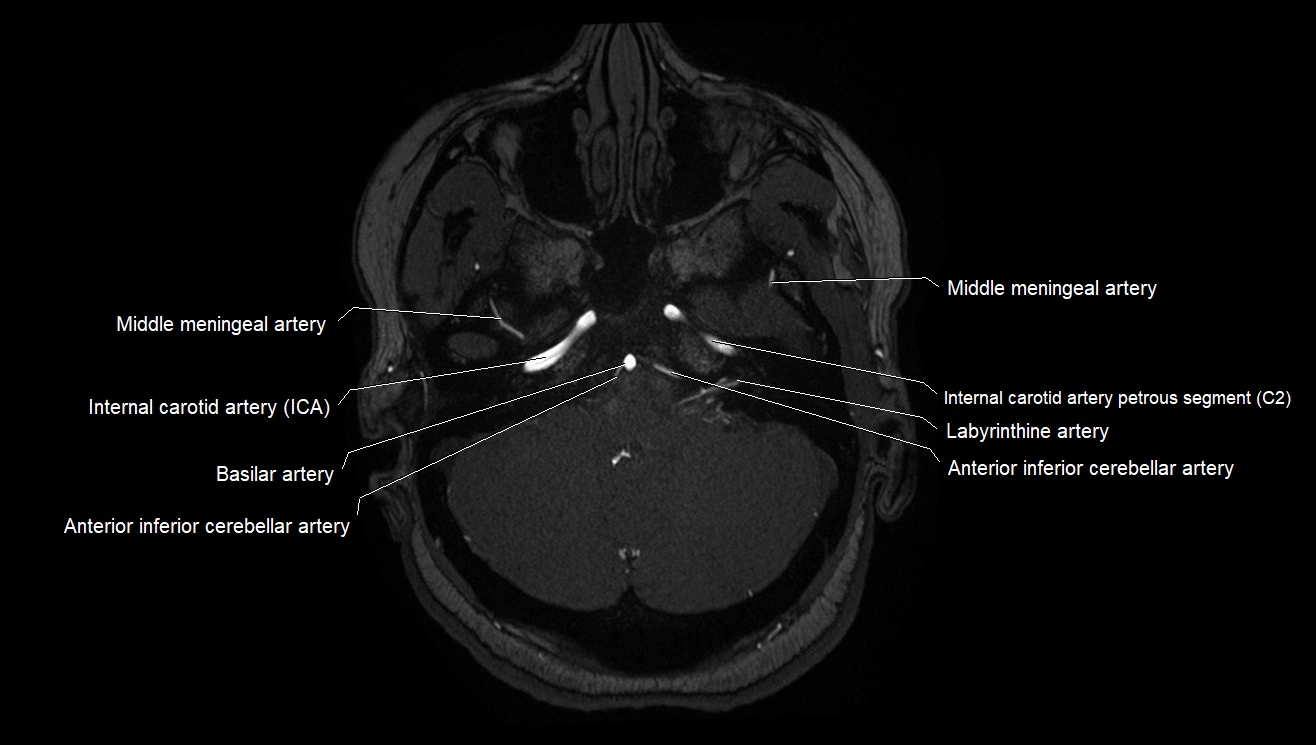

CT images

image